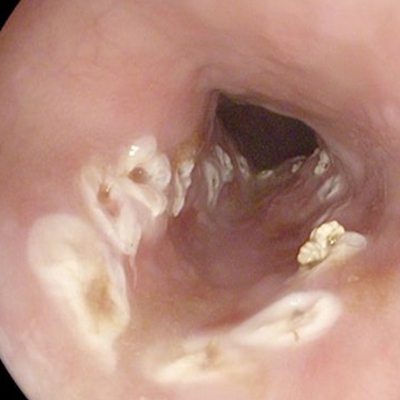

直腸癌圖片

直腸癌晚期症狀 (5)